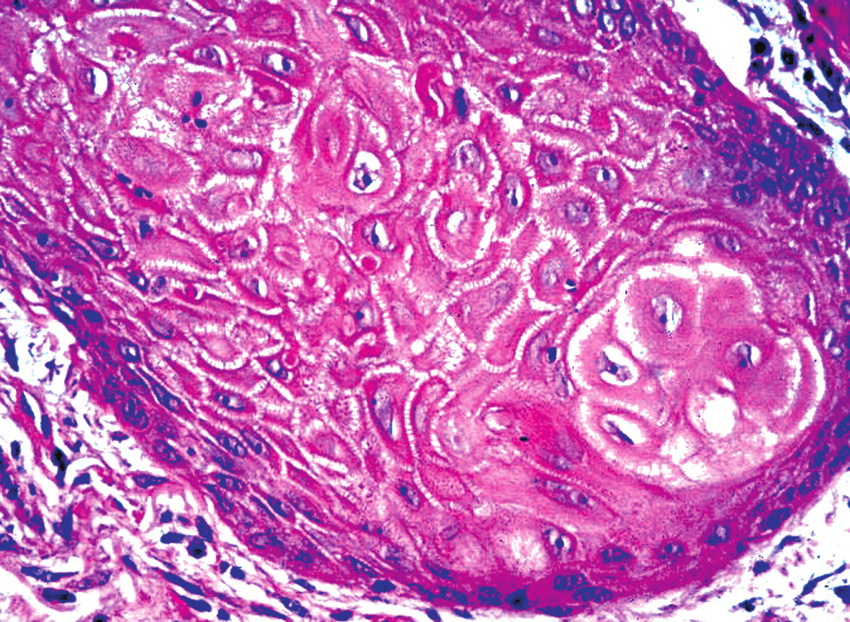

Well-differentiated scc = الكارسينوما الشائكة الخلايا الجيدة التمايز